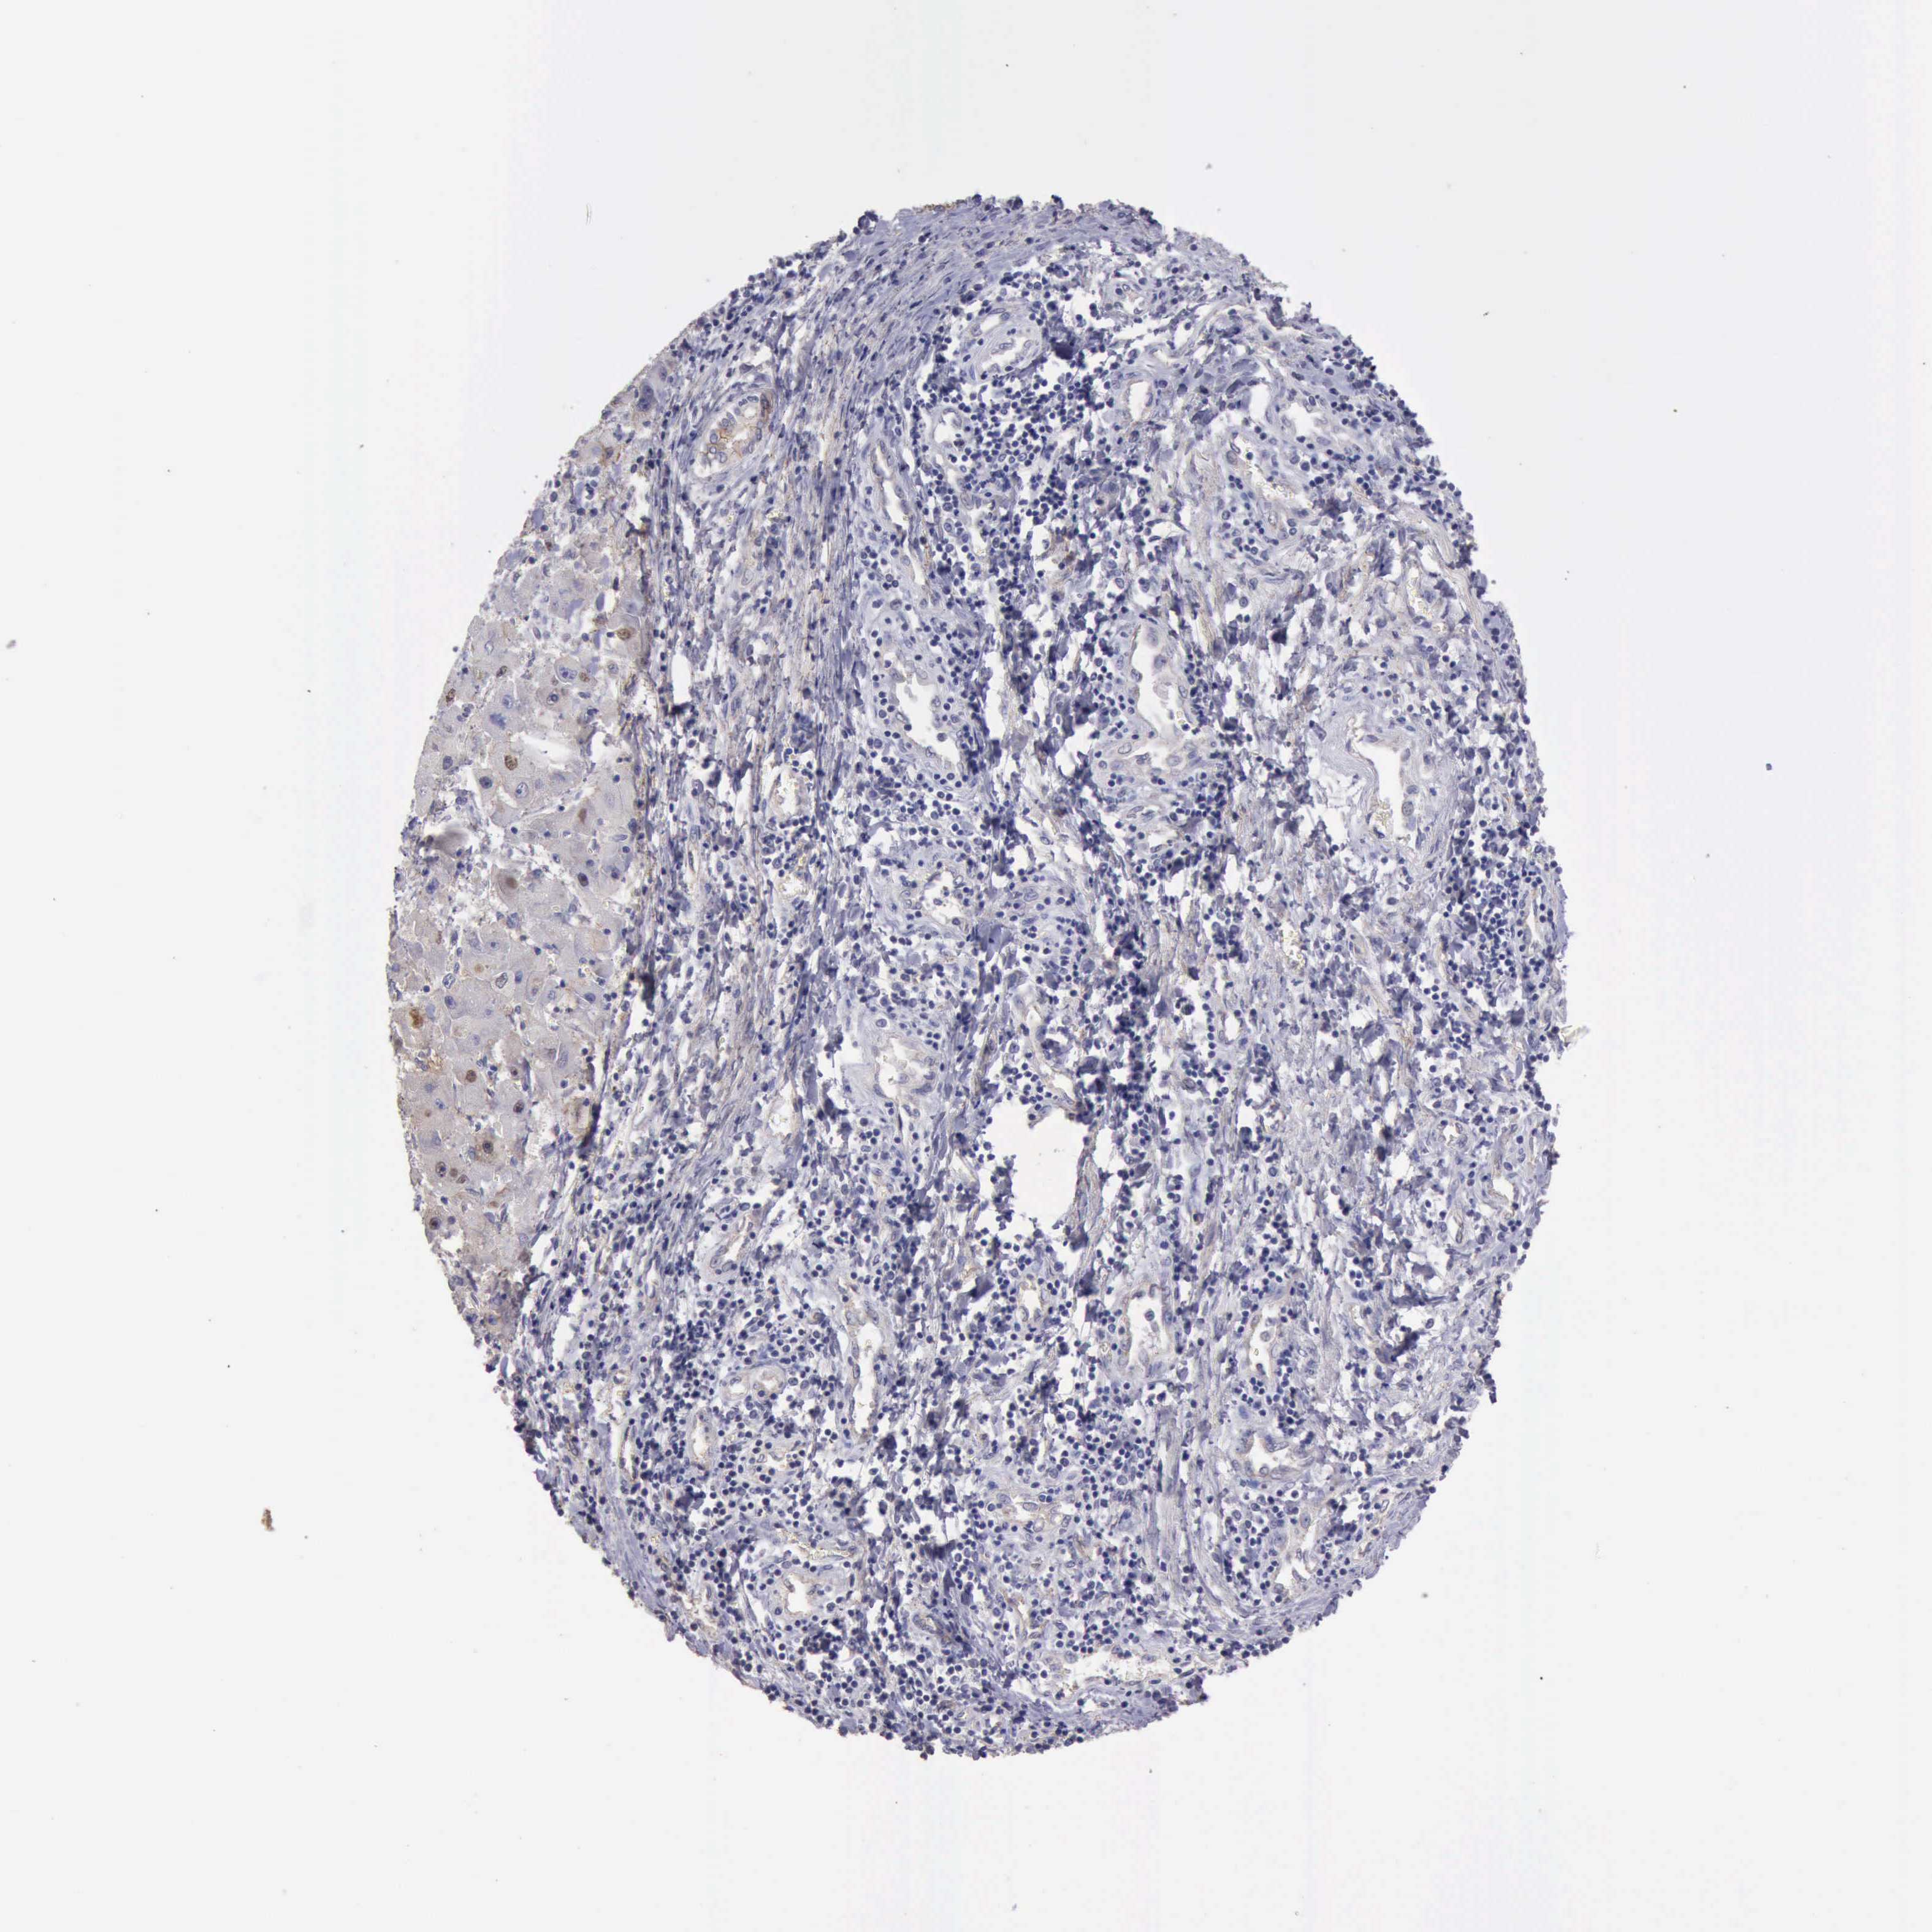

LIVER CANCER - Protein expressioni

A mouse-over function shows sample information and annotation data. Click on an image to view it in a full screen mode. Samples can be filtered based on level of antibody staining by selecting one or several of the following categories: high, medium, low and not detected. The assay and annotation is described here.

Note that samples used for immunohistochemistry by the Human Protein Atlas do not correspond to samples in the TCGA dataset.

Antibody stainingi

Antibody staining in the annotated cell types in the current human tissue is reported as not detected, low, medium, or high, based on conventional immunohistochemistry profiling in selected tissues. This score is based on the combination of the staining intensity and fraction of stained cells.

Each image is clickable and will lead to virtual microscopy that enables deeper exploration of all samples and also displays staining intensity scores, fraction scores and subcellular localization as well as patient and tissue information for each sample.

Antibody HPA001066

Staining

High

Medium

Low

Not detected

Intensity

Strong

Moderate

Weak

Negative

Quantity

>75%

75%-25%

<25%

None

Location

Nuclear

Cytoplasmic/membranous

Cytoplasmic/membranous,nuclear

Carcinoma, Hepatocellular, NOS

Cholangiocarcinoma